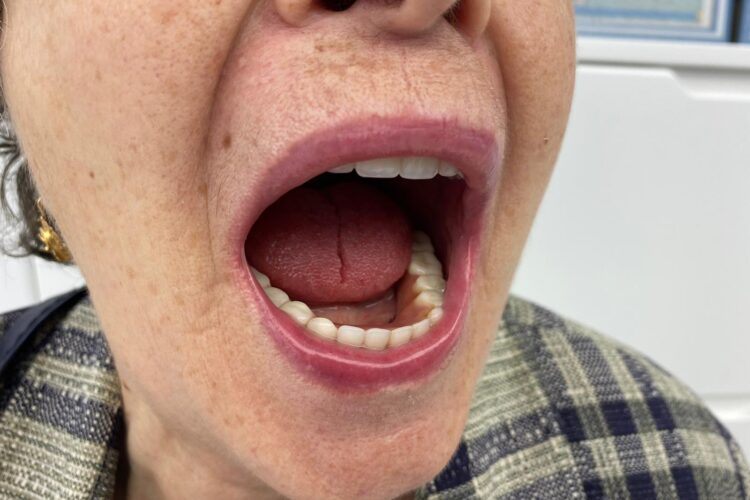

Pacienta in varsta de 75 ani, a pierdut dintii complet la ambele maxilare. Se prezinta in clinica si solicita proteze functionale fixe. Pentru refacerea arcadelor prin solutii implanto-protetice s-au inserat un numar mic de implante (4 implante superior si 4 inferior) care au fost folosite la constructia unei infrastructuri a protezelor, cu bara intre implante, capse laterale si suprastructura armata overdanture. Supraprotezele inserate pe bara satisfac estetica si functionalitatea ca o lucrare dentara fixa.